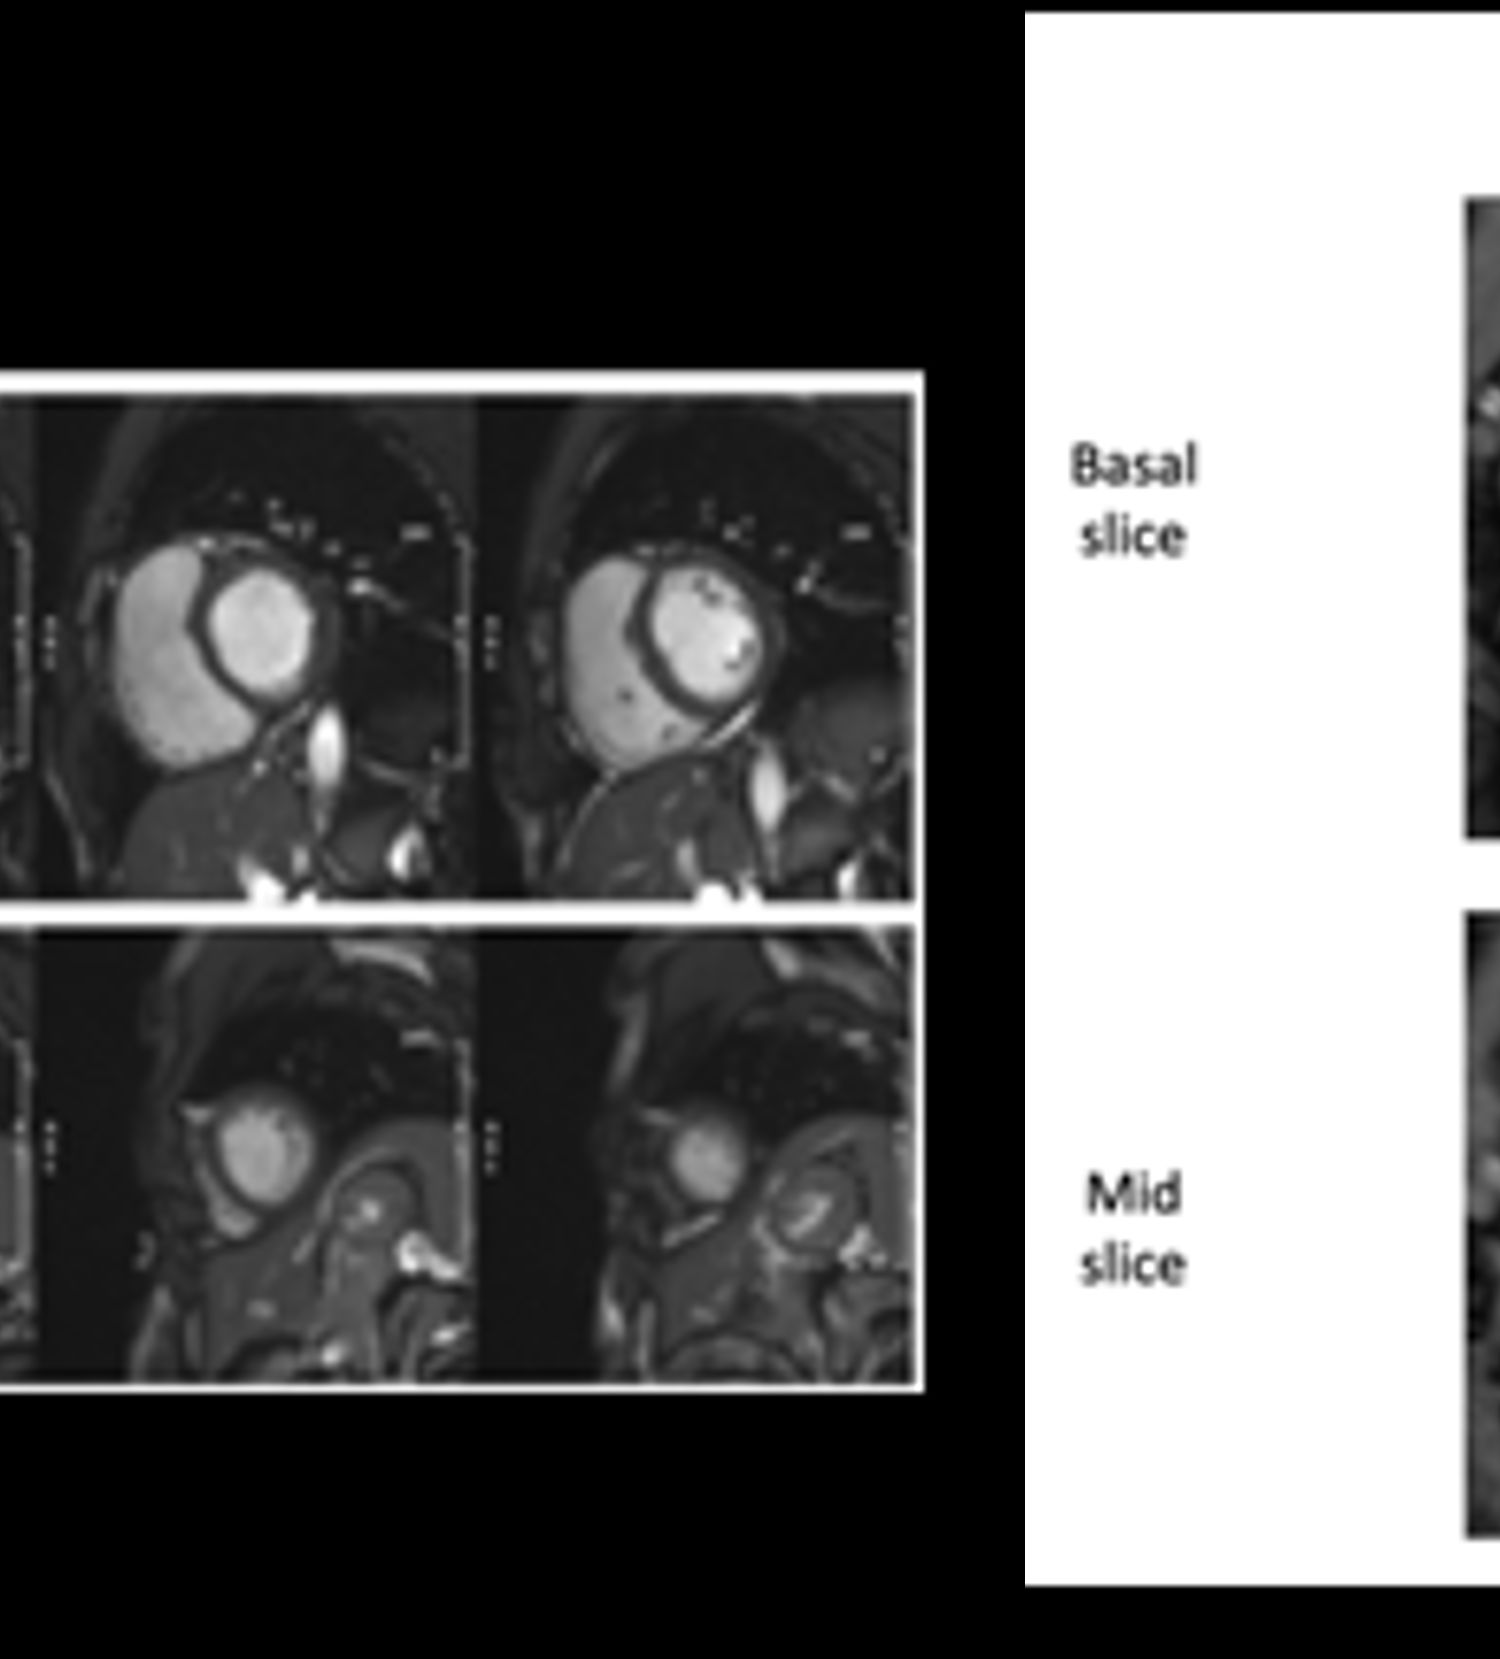

The pilot 2023 program created CMR imaging protocols tailored for producing best quality imaging across participating sites. The SWiM protocols transformed the clinical workflow from the typical single protocol for all clinical indications to protocols designed for common indications, effectively reducing the scan times by 50% while improving CMR image quality. This enables more patients to be scanned and better diagnostic information acquired to guide patient care. The SWiM CMR protocols from participating sites and their scanners are available at the SWiM repository for anyone interested to use.

Enabling Implementation of Advanced MRI in Resource-Limited Settings

One of the aims of SWiM is to accelerate implementation of advanced MRI techniques in resource-limited setting, particularly in LMICs to enable clinical adoption and inclusion in global research. In 2023, advanced CMR techniques such as non-contrast enhanced oxygen-sensitive CMR (OS-CMR) developed by Prof. Matthias Friedrich (McGill University) were introduced at participating sites, leveraging existing standard sequences. The OS-CMR images and quantification values implemented at a participating site during SWiM were comparable and within expected range.